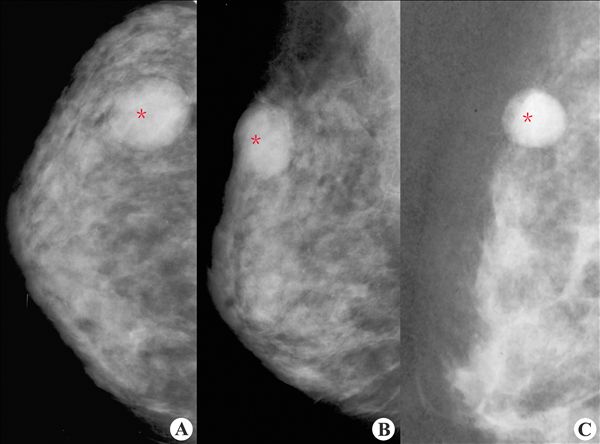

【X线钼靶摄影图片】:

乳腺纤维腺瘤2

【影像表现】:X线(A~C)乳腺组织内示椭圆形高密度影(*),密度均匀医|学教育网整理,边缘光整锐利,其周围出现一层薄的透亮环(透亮晕)。

【影像诊断】:乳腺纤维腺瘤2.